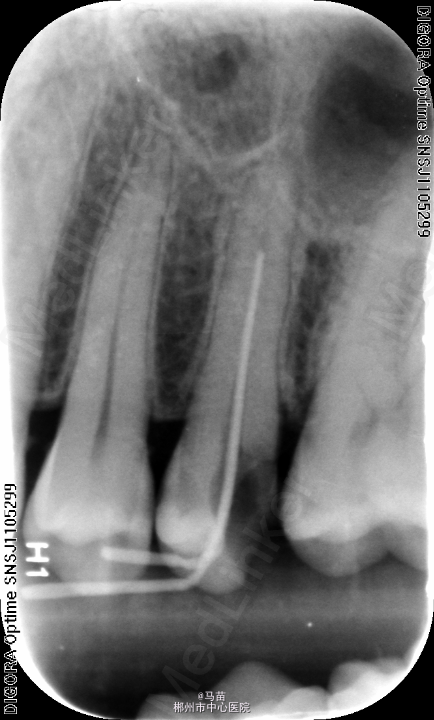

左上5慢性牙髓炎,处理,去腐未尽穿髓,局麻下,开髓揭顶,根管预备第一次测长度17CM,插入牙胶拍片,欠长约3mm,重新清理根尖段牙髓,测长度21CM,完成根管预备及充填

根管预备中,测得长度与估计不符,不能盲目继续根备,最好拍诊断片